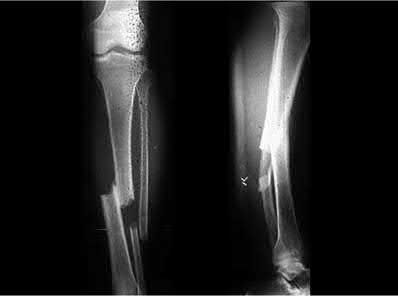

A 55-year-old female presents to the emergency room after falling off her balcony. She sustained the isolated, closed injury shown in Figures A and B. She is otherwise healthy, but routinely smokes 30 cigarettes per day. What would be the most appropriate sequence of treatment steps for definitive management of this injury?

Figures A and B show radiographs of a comminuted AO/OTA C3 fracture of the distal tibia. The most appropriate steps in the management of this patients injury would include: Closed reduction and splinting, external fixation, CT scan, and delayed open reduction internal fixation in this sequence.

Infection and wound healing problems are common with comminuted distal tibia fractures due to an increased incidence of soft-tissue complications associated with the operative management. Patients with a history of diabetes and smoking are at further risk. To decrease the risk of complications in this patient, a two-staged, delayed open reduction internal fixation technique is the best option for the treatment of severe pilon fractures.

Patterson et al. reviewed 23 consecutive patients with comminuted distal tibia fractures. They showed 0% infections or wound-healing problems in their patient population treated with a two-staged protocol. Their protocol involved fibula fixation with an intramedullary implant and application of a medial external fixator to to regain length and restore anatomic alignment. Re-evaluation of the limb occurred ten to fourteen days later for definitive fixation.

Sirkin et al. retrospectively reviewed 40 closed and 82 open pilon fractures (AO types 43A-C) that were treated with staged surgical management (avg. time from ext. fix. to formal reconstruction was 14 days (range 4 to 31) They reported 17% post-operative wound complication in the closed group and 11% post-operative wound complication in the open group (Gustilo Type I-III). They suggest the technique was successful in both closed and open pilon fractures.

Illustration A shows open reduction internal fixation of the above injury. Incorrect Answers:

Answer 1: Universally, nonoperative treatment of OTA/AO C3 fractures has led

to poor outcomes.

Answer 2,3: Although Ruedi and Allgower (1969) were the first to report successful results with primary open reduction and internal fixation of low-energy fracture patterns, few studies have achieved good results with low soft-tissue complications.

Answer 4: CT scan is most appropriate after frame application. This will allow for distraction and indirect reduction of the fragments to better characterize the fracture pattern for pre-operative planning.